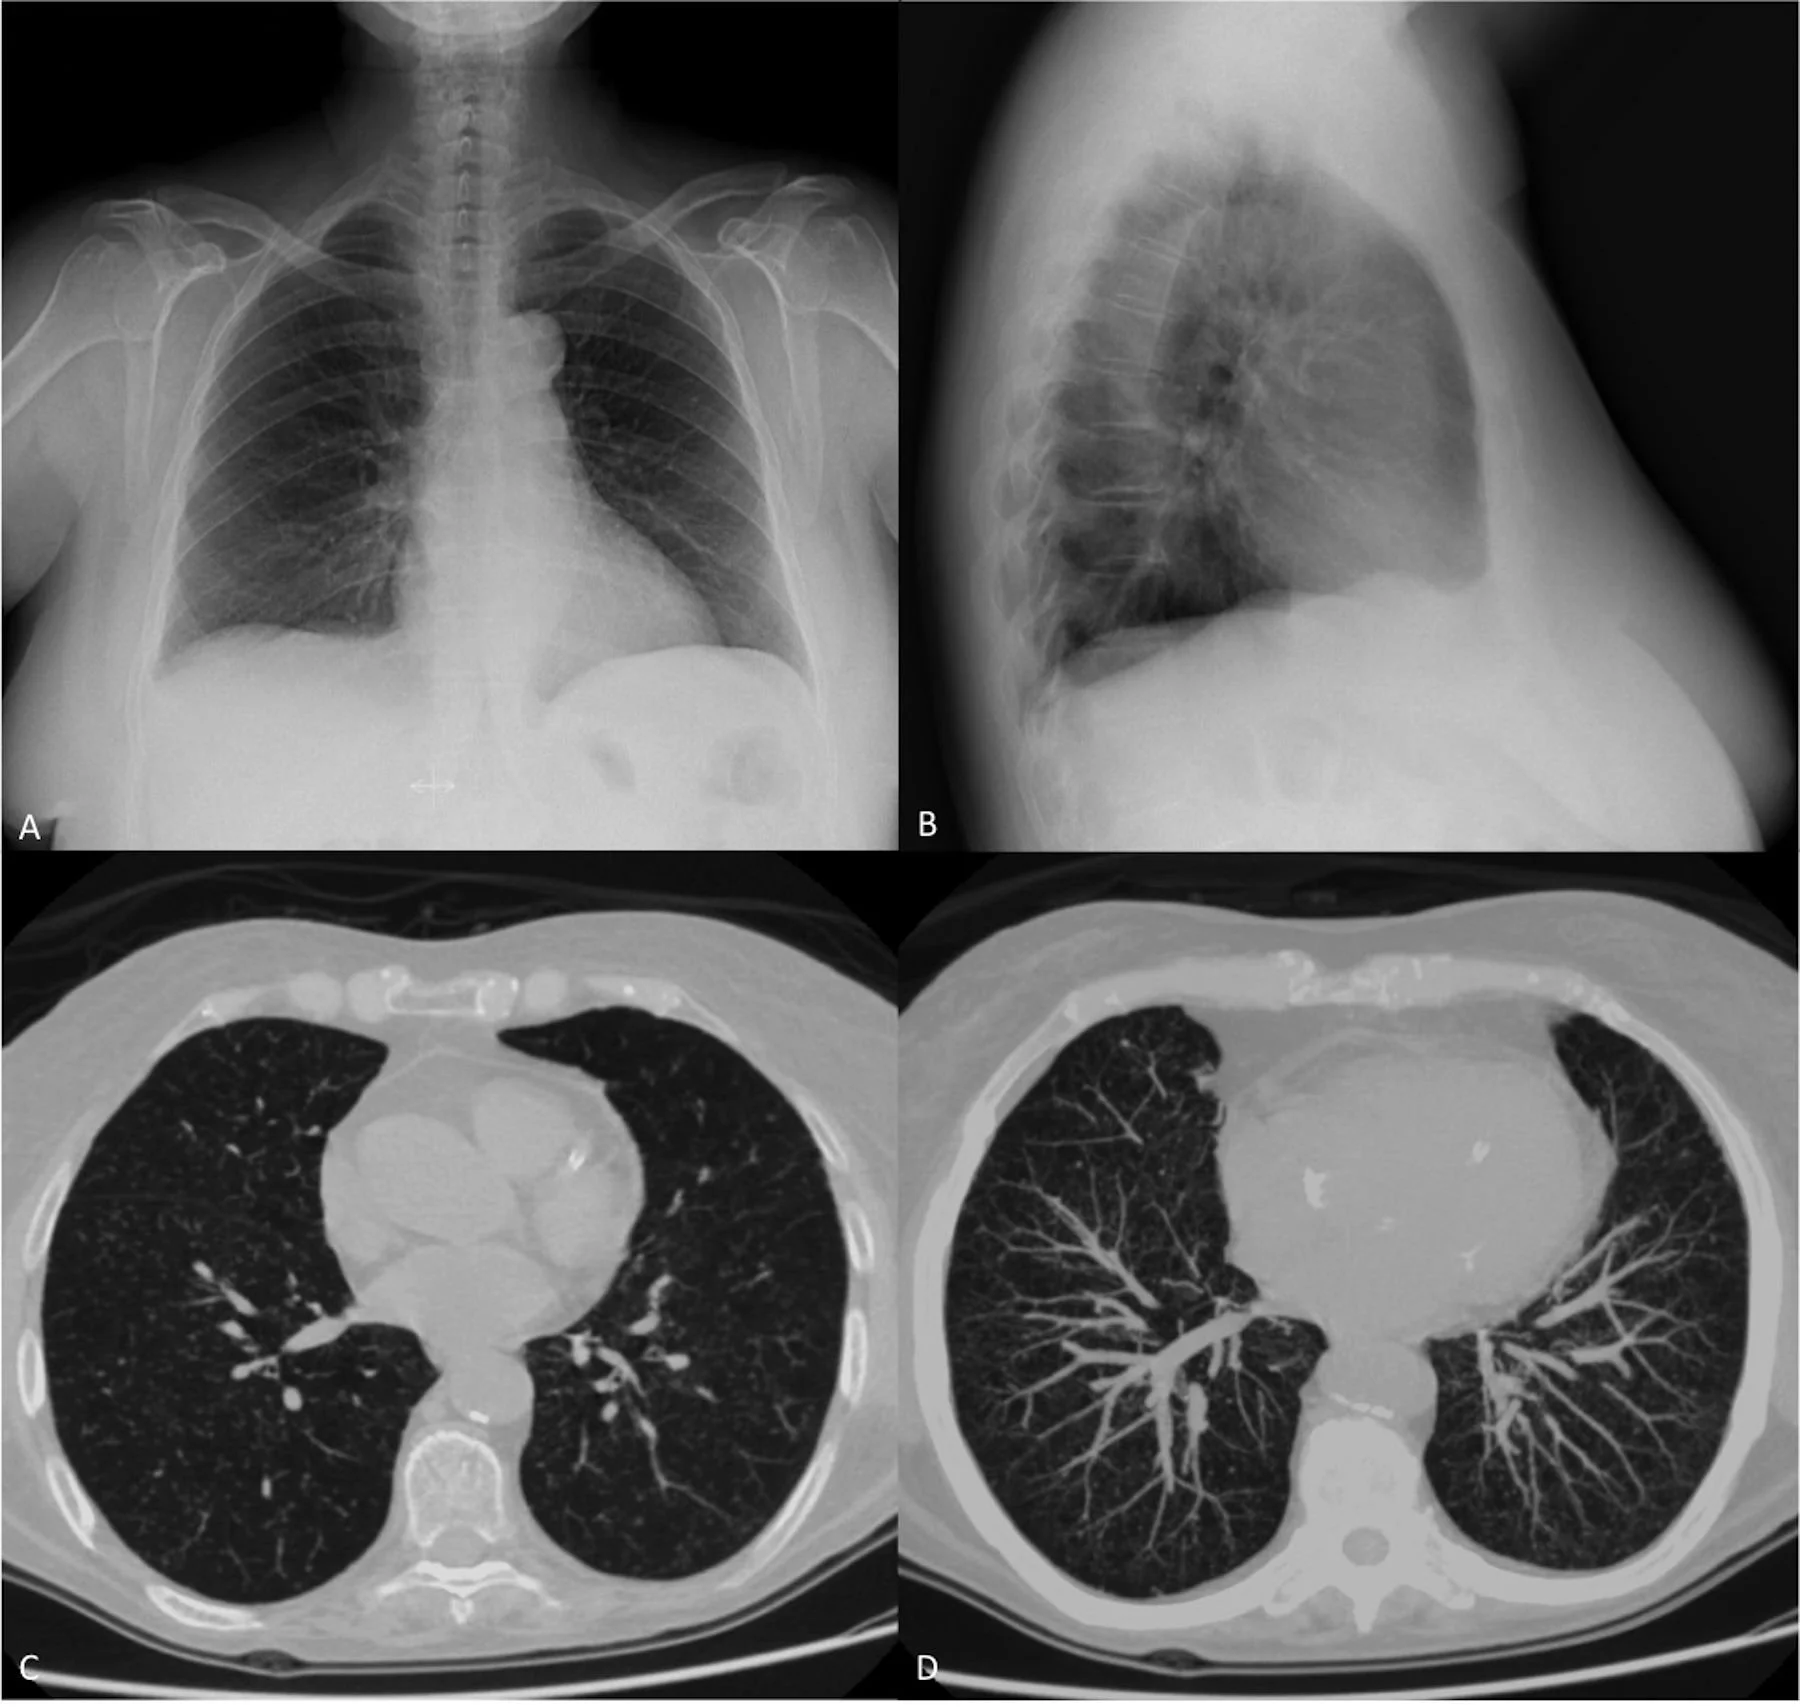

Tuberculosis is an infectious bacterial disease that mainly affects the lungs but can also spread to other parts of the body such as the brain, kidneys, or spine. It is caused by the bacterium M. tuberculosis, which spreads through the air when a person with active TB in their lungs coughs, sneezes, or speaks, meaning it is airborne. When an individual inhales these bacteria, they enter the lungs and start to multiply.

Active TB disease – If the immune system cannot control the bacteria, they multiply and damage lung tissue, leading to symptoms like coughing, fever, weight loss, and fatigue.